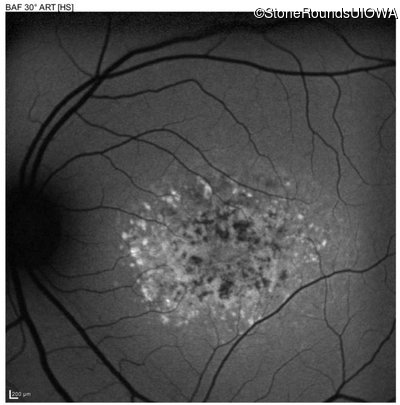

This 16 year old female first had difficulty seeing the blackboard at age 9. Her eye doctor at the time felt at the time that she was "faking it". More recently her eye doctor told her she would be blind by age 20 and suggested she get a seeing eye dog.

| AR Stargardt Disease | ABCA4 | Asp507Tyr GAT>TAT | IVS40+5 G>A | AR |